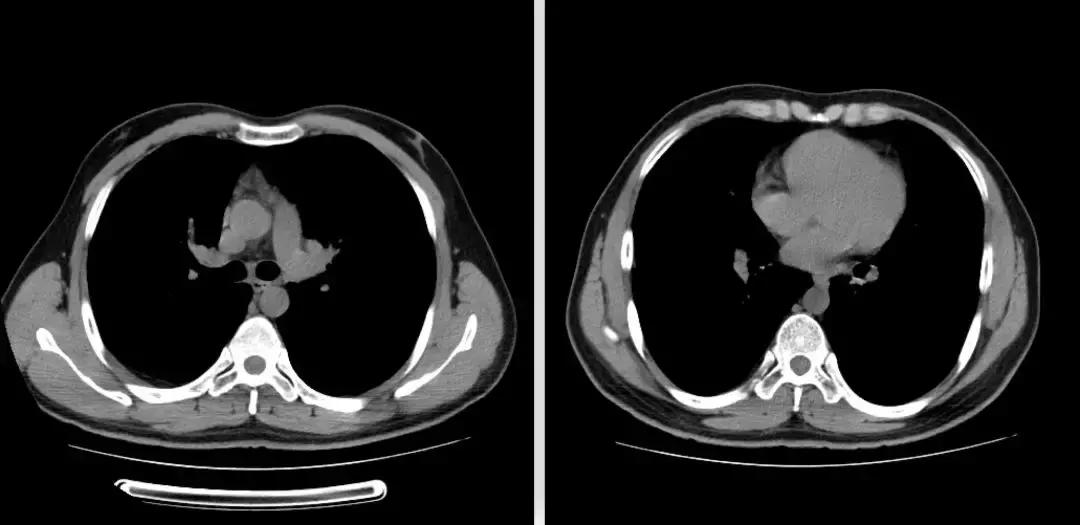

2018-01-22行支气管镜检查:示两侧支气管粘膜充血明显,可见少量白色分泌物,充分吸引;于左下叶生理盐水20ml灌洗2次,回吸收均约10余ml;左上叶、左下叶刷检,刷片共6张。(气管镜报告如下图)。

隆突 右上叶

右中叶 右下叶

左上叶 左下叶